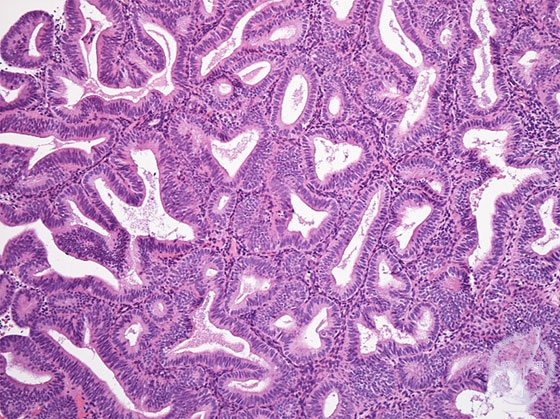

- ★(5)Complex endometrial hyperplasia

Histology (HE stain, intermediate power): Endometrial hyperplasia, complex. Proliferation of endometrial glands without cytologic atypia, forming dense and complicated architecture (yellow dotted line). Stromal proliferation is obscure.